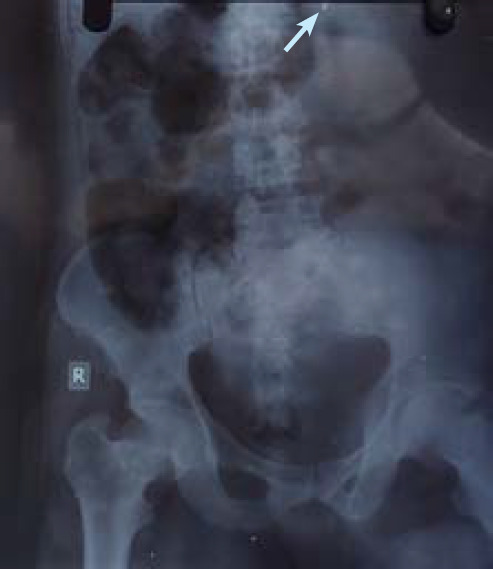

火器伤害会导致不同程度的创伤,这取决于火器类型、射程和伤口位置等因素。本病例报告介绍了x射线成像在检测造成致命穿透性腹部创伤的弹丸中的作用。发现病人腹部有枪伤,尽管进行了医疗干预,他还是因伤势过重而死亡。x射线成像显示腹腔内有一个高密度区域,类似子弹。尸检证实是近距离枪击造成腹膜,肠系膜,肝脏严重内部损伤,子弹落在L1椎体附近。该病例强调了放射成像在识别弹丸轨迹和损伤严重程度方面的价值,特别是在资源有限的情况下。x射线有助于区分穿透性和穿孔性伤口,有助于法医调查和法律程序。影像在法医尸检中的整合提高了损伤评估的准确性,特别是在涉及枪伤的情况下。

Firearm injuries can result in varying degrees of trauma, depending on factors such as the type of firearm, range, and wound location. This case report presents the role of X-ray imaging in detecting a projectile causing fatal penetrating abdominal trauma in a 45-year-old male. The patient was found with a gunshot wound in his abdomen, and despite medical interventions, he succumbed to his injuries. X-ray imaging revealed a hyper-dense area resembling a bullet lodged in the abdominal cavity. Autopsy confirmed a close-range gunshot with significant internal damage to the peritoneum, mesentery, liver, and the bullet lodged near the L1 vertebra. This case underscores the value of radiological imaging in identifying projectile trajectory and injury severity, particularly in resource-limited settings. X-rays assist in distinguishing between penetrating and perforating wounds, aiding both forensic investigation and legal procedures. The integration of imaging in forensic autopsies improves the accuracy of injury assessment, especially in cases involving gunshot wounds.